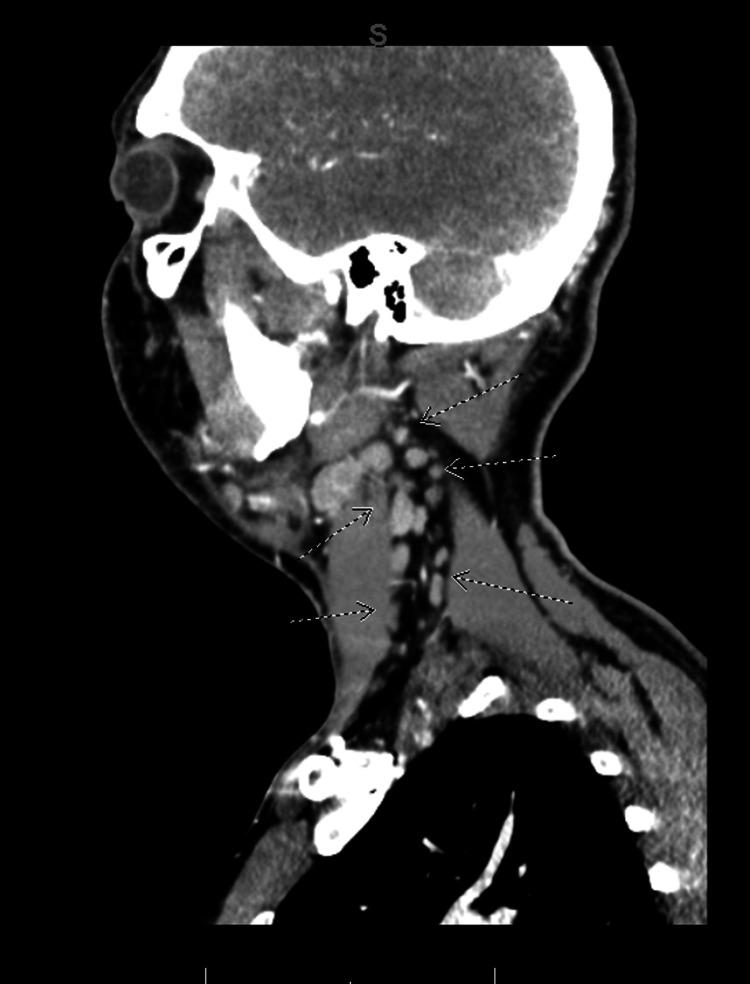

Lemierre's syndrome is a rare and potentially life-threatening complication of head and neck infections, such as bacterial pharyngitis or tonsillitis. It is characterized by the extension of infection into the lateral pharyngeal spaces, leading to subsequent septic thrombophlebitis of the internal jugular vein(s). Although relatively uncommon since the advent of appropriate antibiotic therapy, the incidence of Lemierre's syndrome has increased in the past 15 years, especially among young, healthy adults. This increase is likely attributed to the increasing prevalence of oropharyngeal infections in this population, making an initial diagnosis of Lemierre's syndrome often elusive on presentation. Delayed recognition of this syndrome can result in treatment delays, increasing the morbidity and mortality in this condition. The diagnosis of Lemierre's syndrome is typically confirmed through the identification of thrombophlebitis of the internal jugular vein on radiographic imaging and the isolation of anaerobic bacteria in blood cultures. Treatment involves prolonged antibiotic therapy and, often, anticoagulation. This case report presents a rare complication of bacterial tonsillitis, with initial imaging that demonstrated left peritonsillar phlegmon and subtle micro-occlusions of the left internal jugular vein on early imaging. Within four days, the infection rapidly progressed to complete occlusion of the internal jugular vein with pulmonary septic emboli, culminating in Lemierre's syndrome. This case highlights the importance of early detection and treatment of subtle radiographic findings of thromboses, along with consideration of social determinants of health, in the setting of head and neck infections to avoid rapid progression to Lemierre's syndrome, a disease with an elusive initial presentation and potentially fatal outcomes.

勒米尔综合征是头颈部感染(如细菌性咽炎或扁桃体炎)的一种罕见且可能危及生命的并发症。其特征是感染蔓延至咽旁间隙,继而导致颈内静脉脓毒性血栓性静脉炎。自适当抗生素疗法问世以来,虽然相对不常见,但勒米尔综合征的发病率在过去15年中有所上升,尤其是在年轻健康的成年人中。这种上升可能归因于该人群口咽感染患病率的增加,使得勒米尔综合征在初诊时常常难以确诊。对该综合征的延迟识别可能导致治疗延误,增加该病的发病率和死亡率。勒米尔综合征的诊断通常通过影像学检查发现颈内静脉血栓性静脉炎以及血培养中分离出厌氧菌来确诊。治疗包括长期抗生素治疗,通常还需要抗凝治疗。本病例报告呈现了一例细菌性扁桃体炎的罕见并发症,早期影像学显示左侧扁桃体周围蜂窝织炎以及左侧颈内静脉细微的微血栓形成。在四天内,感染迅速进展为颈内静脉完全闭塞并伴有肺脓毒性栓子,最终发展为勒米尔综合征。该病例强调了在头颈部感染的情况下,早期发现和治疗血栓形成的细微影像学表现的重要性,并考虑健康的社会决定因素,以避免迅速发展为勒米尔综合征,该病初发表现隐匿且可能导致致命后果。